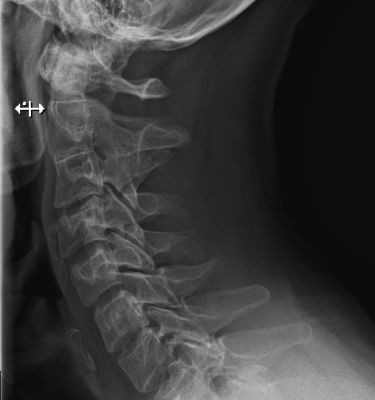

Диагнозы ставятся на основании МРТ или КТ шейного отдела, УЗИ сосудов головы и шеи, осмотра врачом и проведения тестов.

Для уточнения диагноза может понадобиться консультация ЛОРа, эндокринолога, пульмонолога, травматолога, психиатра и т.д. УЗИ щитовидной железы, рентген шеи, флюорография, анализ крови/мочи и т.д. При сборе анамнеза можно исключить лишние обследования и обращения к врачам.

Больному рекомендуется провести МРТ шейного отдела и обратиться к врачу. Из методов лечения, которые применяются в условиях клиники:

Выявление источника возникновения болевых ощущений в затылке, поясничном отделе, спине, ушах и какой-либо другой локализации в процессе наклона головы нуждается в комплексном подходе.

Из этого можно сделать вывод, что диагностика предполагает:

- всесторонний опрос больного – в целях составления клинической картины, установления временных отрезков возникновения и степени тяжести выраженности основной симптоматики либо вспомогательных признаков;

- изучение анамнеза заболевания и жизнедеятельности пациента;

- объективный осмотр – в целях уточнения расположения дискомфорта в процессе наклонов головы назад;

- клинические анализы – для контроля над работой органов и систем внутри организма, для установления симптомов воспалений, инфекций либо какой-либо иной патологии;

- инструментальная диагностика пациента – основной является УЗИ, рентгенограмма и КТ.